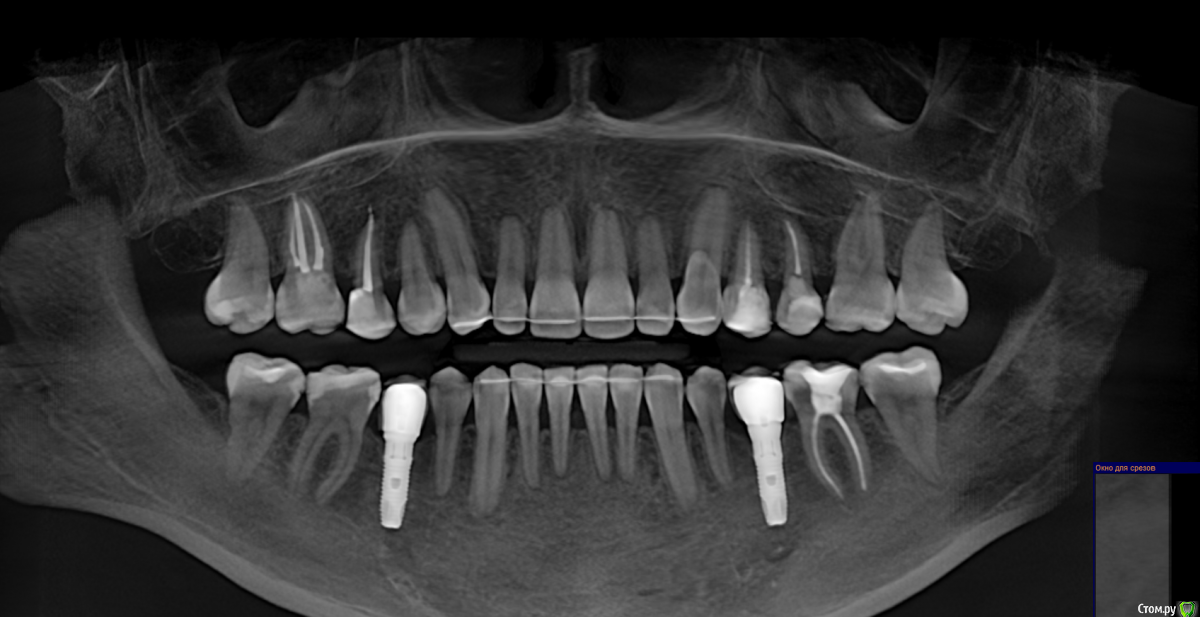

Добрый день! Два месяца назад началась моя история с зубами. Беспокоили дикие боли в зубах, как при пульпите, в 4-ке и 5-ке. Сделано было несколько прицельных и рентгеновских снимков, которые ничего не показали. Обошла пять стоматологов, никто проблем не находил, отправляли к лору или неврологу. КТ никто сделать не предложил, к сожалению. Было принято решение совместно с шестым! стоматологом депульпировать эти два зуба. При удалении нервов стоматолог сказал, что нервов уже почти нет и в 4, и в 5, сказал, что у меня хронический периодонтит, а в 4-ке стоматолог увидела на снимке (когда проверяла каналы после лечения) наружную резорбцию корня. В 5-ку поставили сразу постоянную пломбу, в 4-ке сейчас стоит временная (материал МТА). Но боль в 4-ке осталась, она не такая конечно сильная, как была, но ноющая, усиливается после горячего, после еды, в основном. И над зубом есть свищ, он не беспокоит и не болит при надавливании (стоматолог говорит, что это материал под десной, из-за резорбции) Врач говорит, что все пройдет, и через 2 месяца ставим постоянную пломбу, но болит уже месяц. Я сама сделала КТ, очень прошу вас посмотреть и подсказать, как действовать дальше? Может проще удалить этот зуб и поставить имплантат?